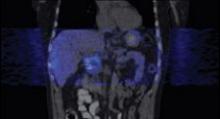

June 27, 2007 - Imaging Diagnostic Systems Inc. announced the release and publication of select results highlighting the advantages of using CT laser breast imaging as an adjunct to conventional mammography to improve detection of occult cancers in dense breasts.

"These CTLM results are being released as a response to the growing number of requests for performance statistics received from distributors and prospective customers worldwide. The results were obtained from our initial PMA-designed clinical study," commented Tim Hansen, IMDS Chief Executive Officer.